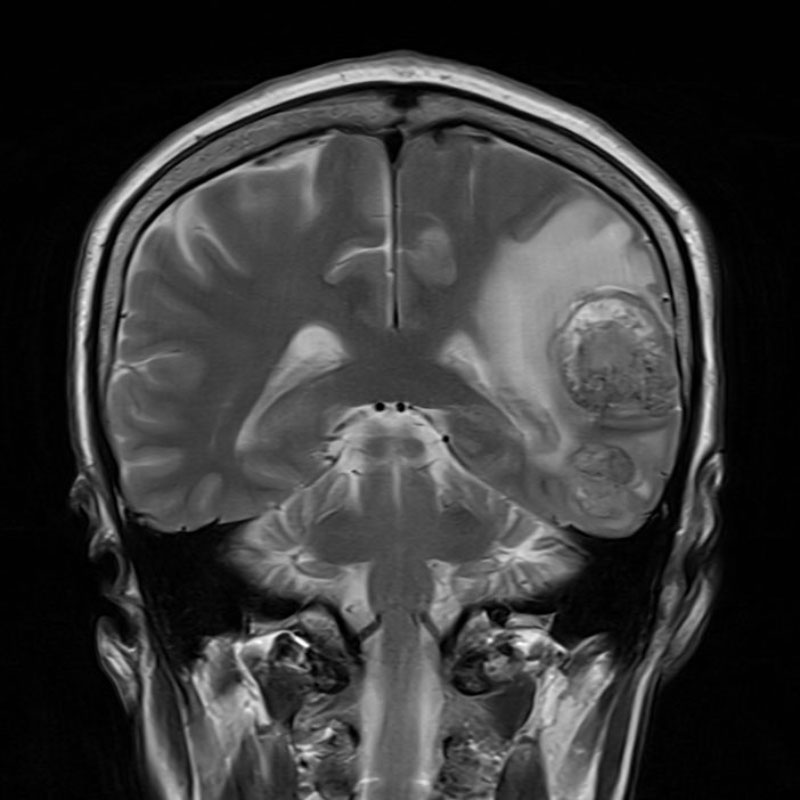

706

'25年12月

80代

右頭頂葉腫瘍

頭蓋内腫瘍摘出術